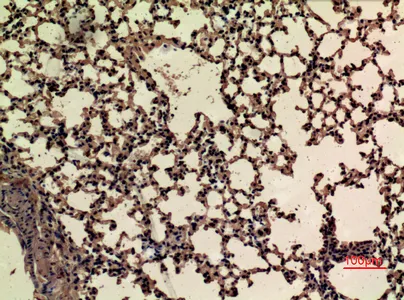

CD68 Rabbit Polyclonal Antibody

Cat: APRab08436

Size1:50μl Price1:$118

Size2:100μl Price2:$220

Size3:500μl Price3:$980